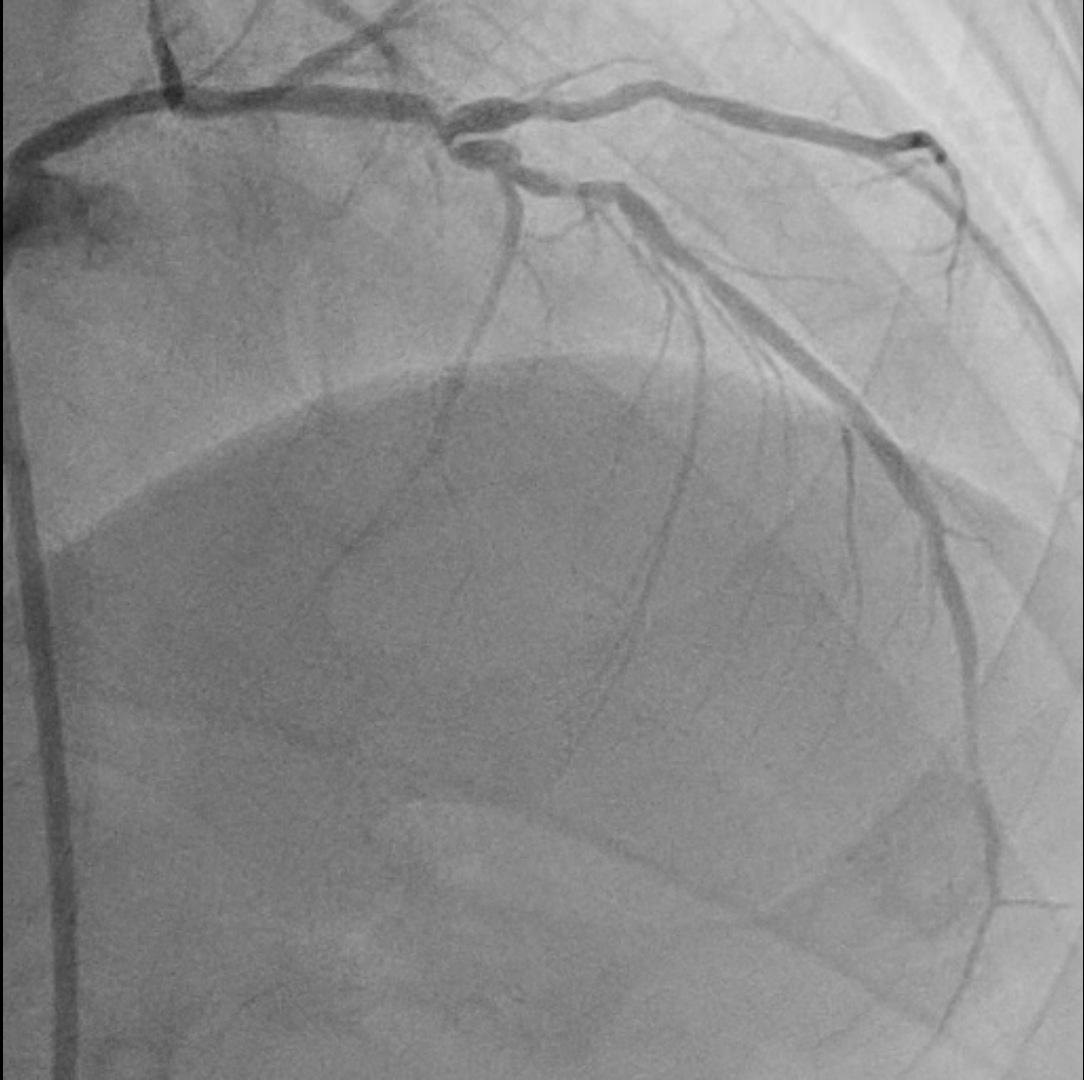

Relevant Catheterization Findings

Coronary angiography examinationresults, we found patient with severe stenosis in proximal-mid LAD with tortuous andradiopacities seen before contrast injection in the arterial wall (tram-trackappearance) looks like calcifed lession and patent stent from Left main to LCx, non signifikan lession in right coronary artery.